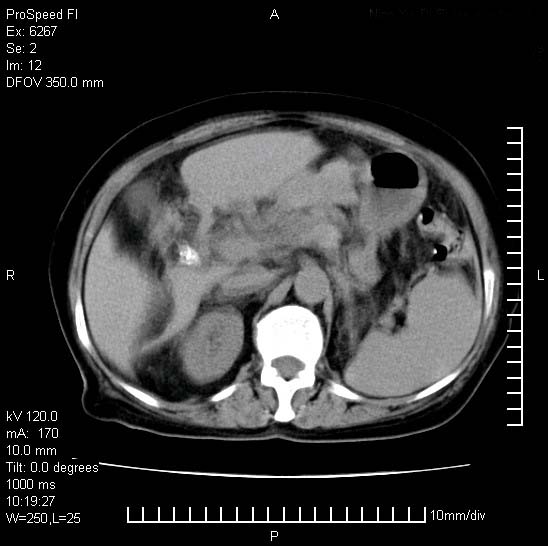

患者糖尿病,腹痛,恶心,呕吐。黄疸,意识较差,血糖很低(数值不详),临床以胆囊,胆管炎,低血糖反应收治。看的腹片少,各位帮忙看看,胰腺有问题吗??

1.胰腺体积增大,胰周脂肪间隙消失,胰腺炎可以确定。必要时实验室进一步检查。

2.胆囊炎,胆石症。

胰腺体积增大,胰周脂肪间隙消失,考虑胰腺炎。胆囊炎,胆石症。

脾大,原因?胆结石;胰腺肿大,边缘模糊,建议查定性指标血尿淀粉酶,除外胰腺炎